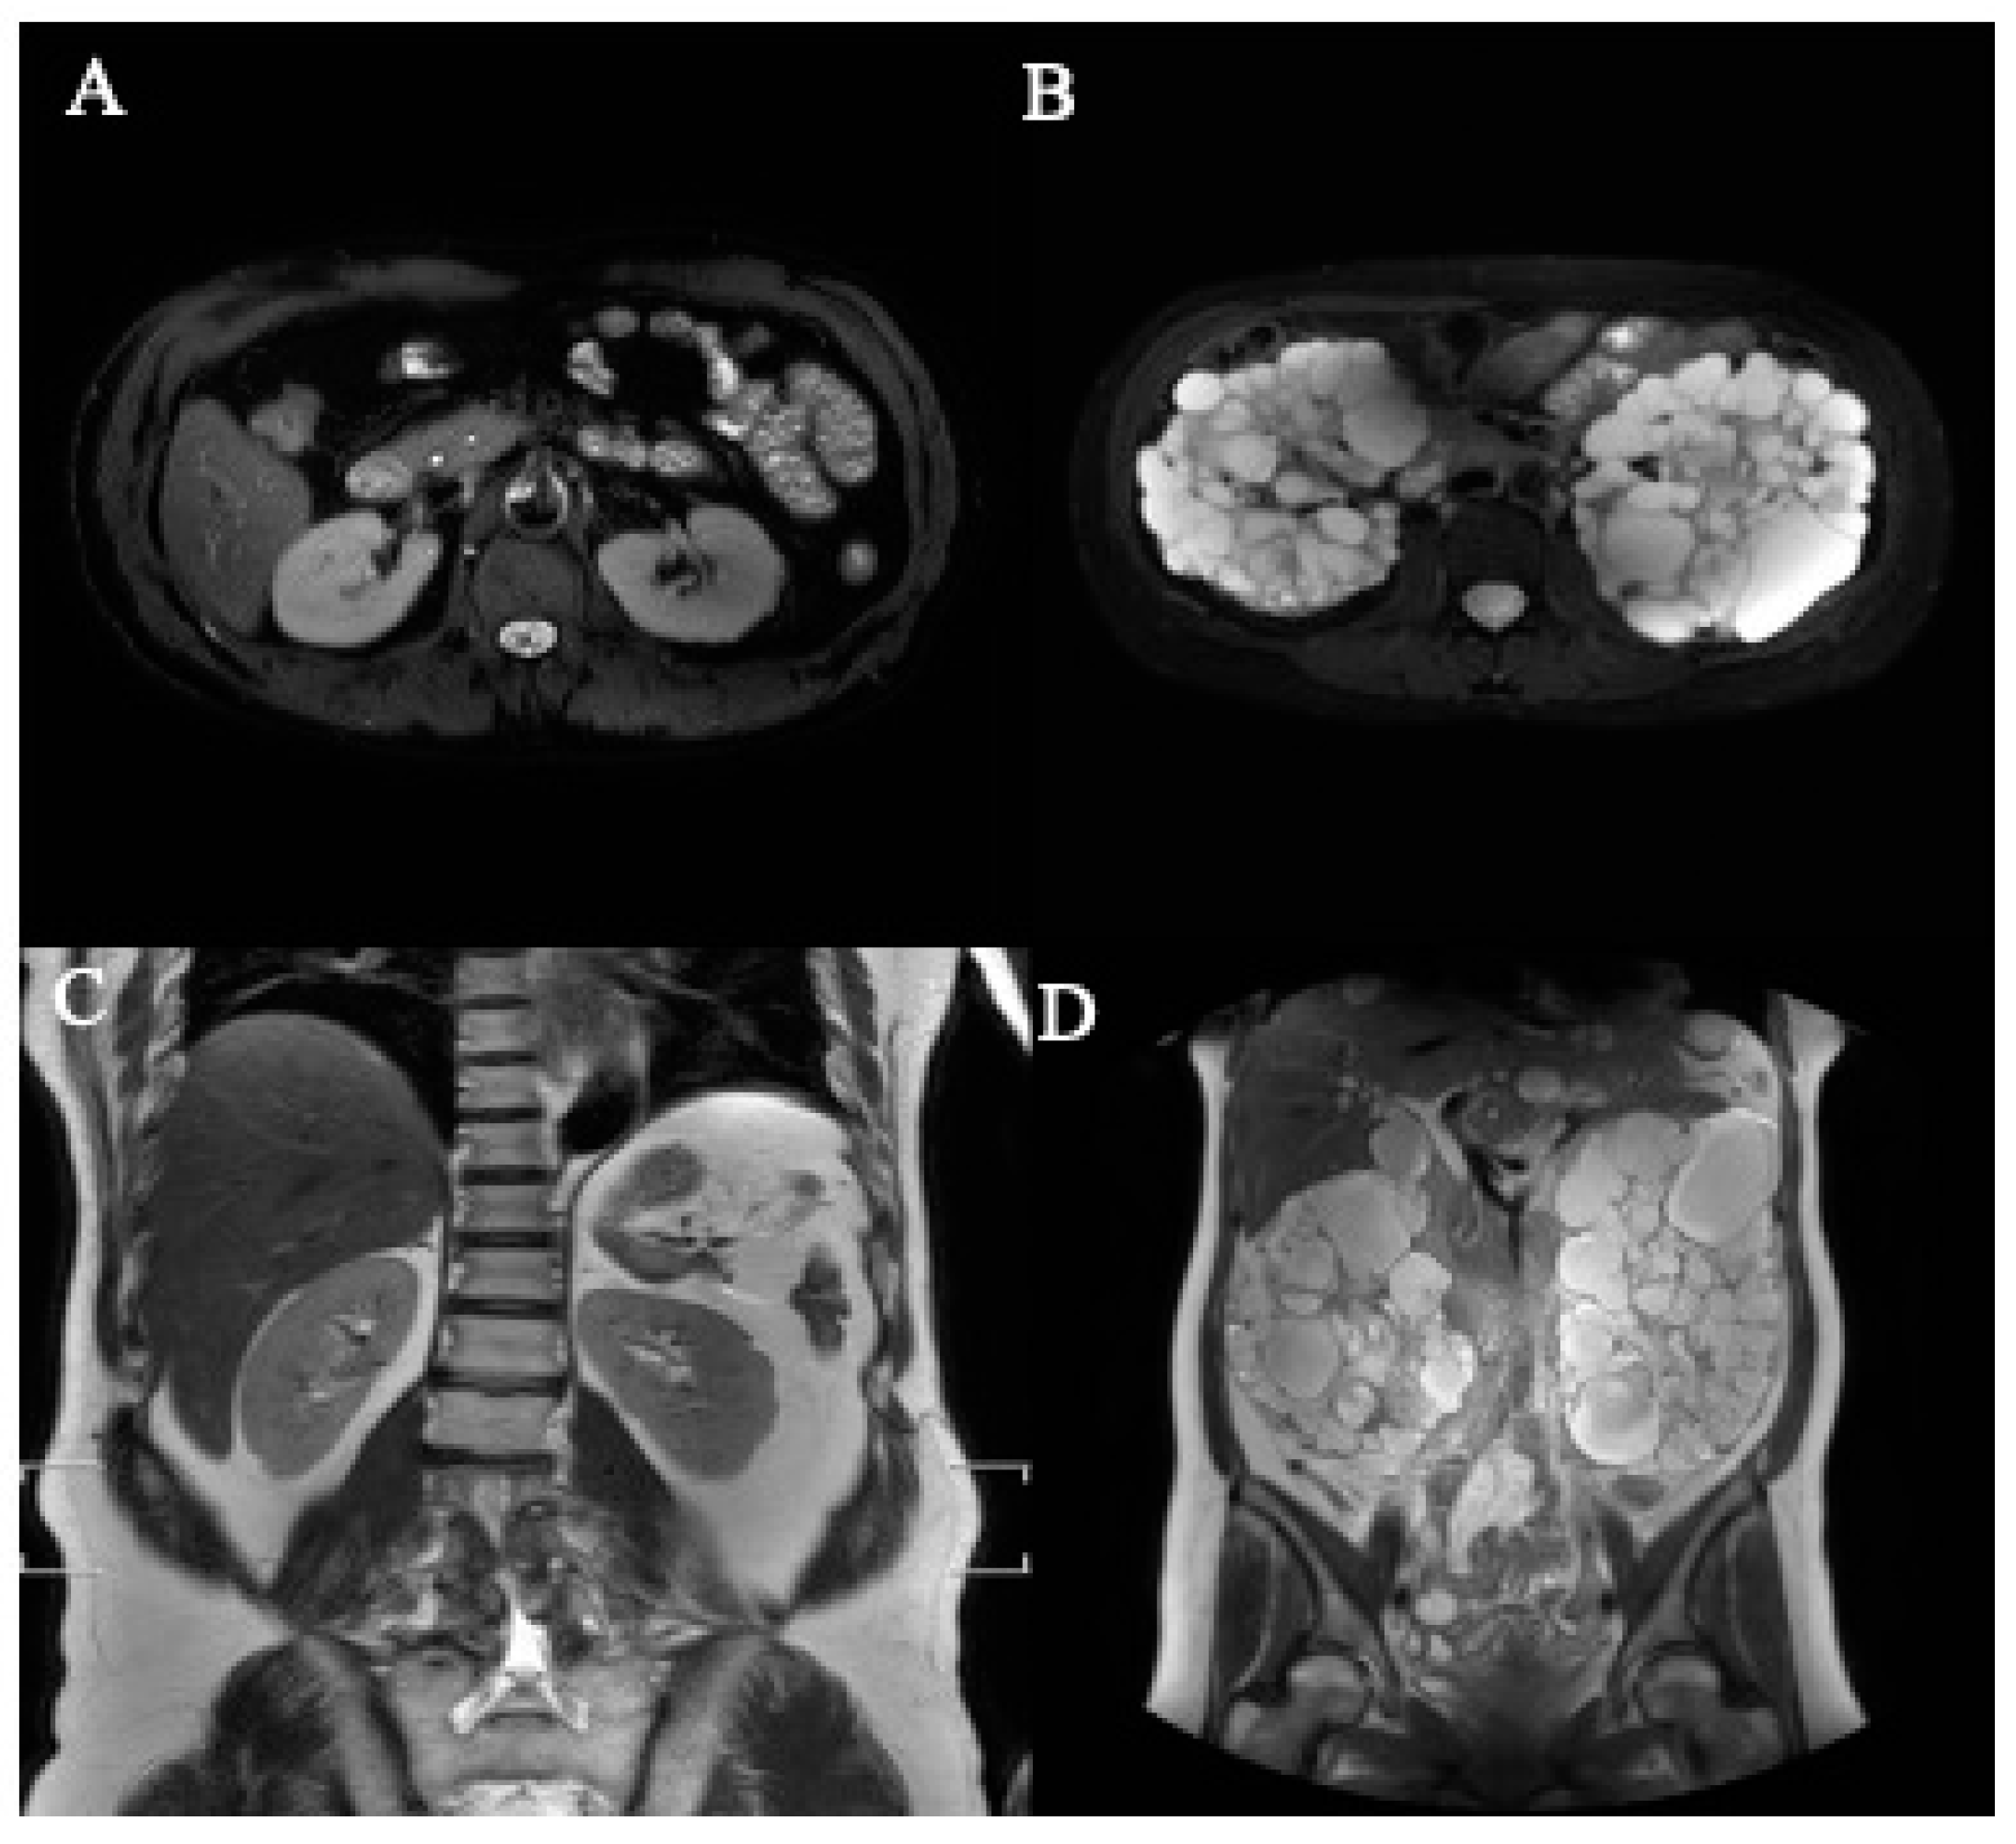

2.4. Data Labeling and Management

3.3. Accuracy of Segmentation